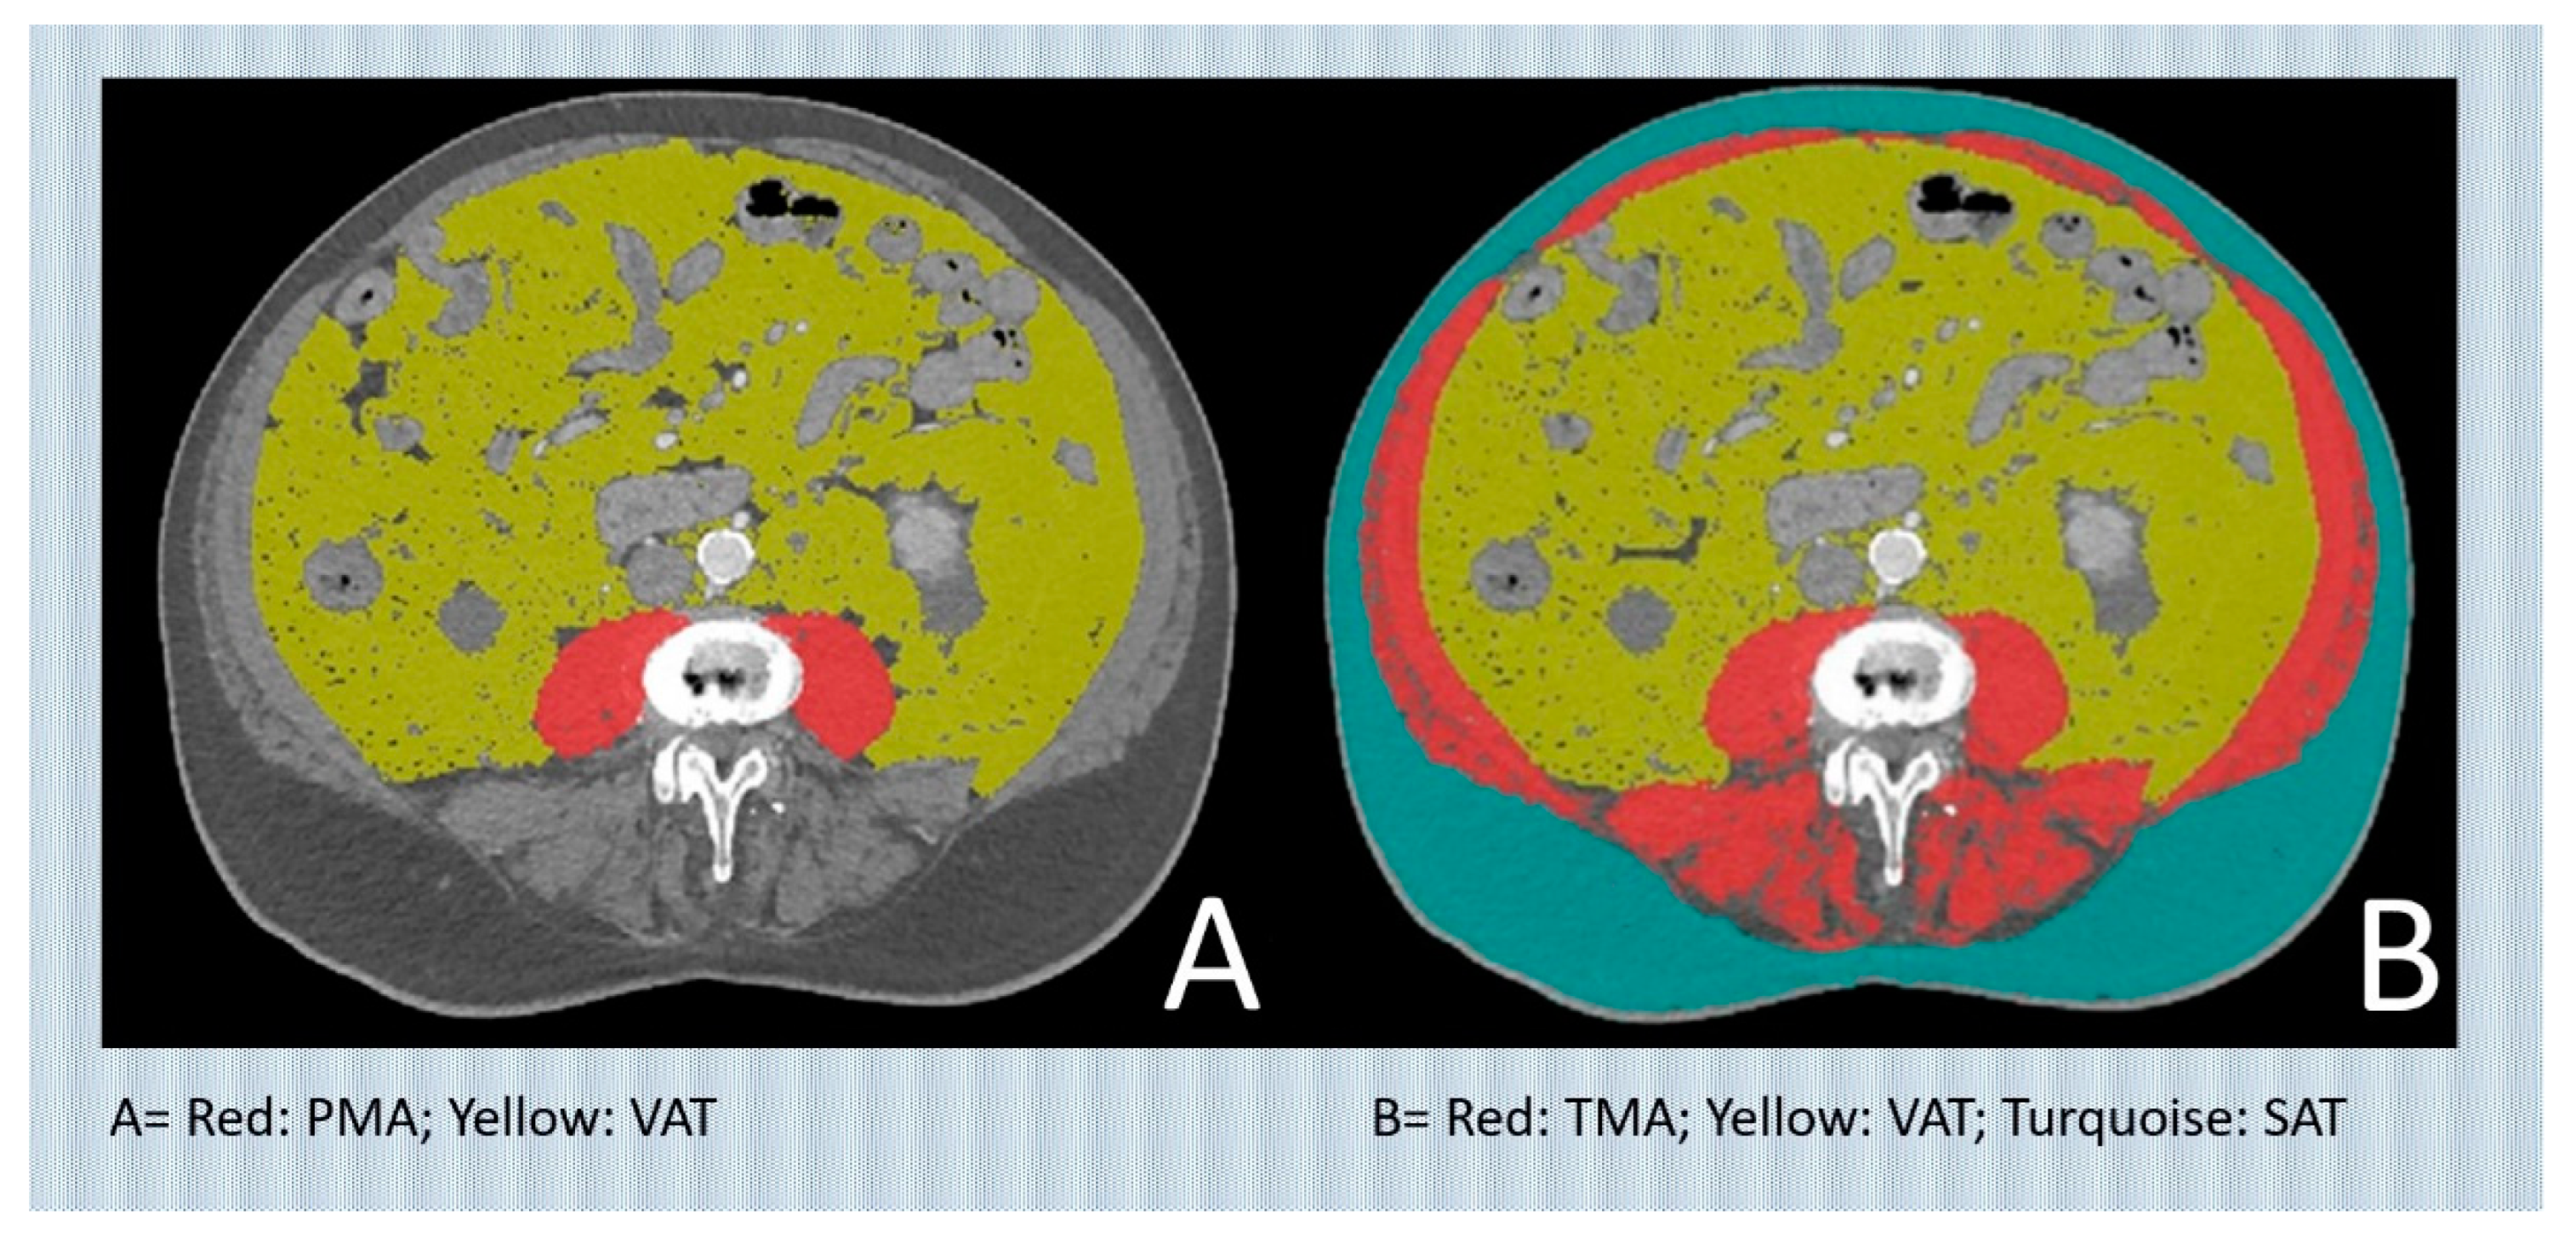

| TMA | Total muscle area |

| nTMA | normalized total muscle area |

| PMA | Psoas muscle area |

| VAT | Visceral adipose tissue |

| Visceral adipose tissue (cm2) | 134 [68.5;216] |

| Total muscle area (cm2) | 110 [93.4;131] |

| Total muscle Area normalized by body surface area (-) | 62.3 [54.5;70.1] |

| Subcutaneous adipose tissue (cm2) | 148 [106;207] |